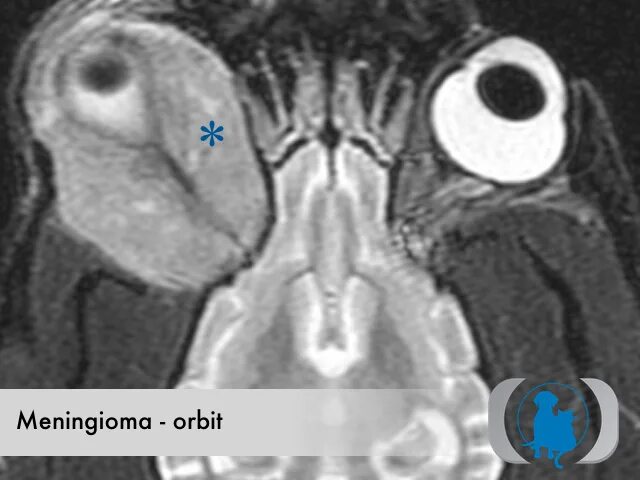

Мрт орбит и зрительных нервов